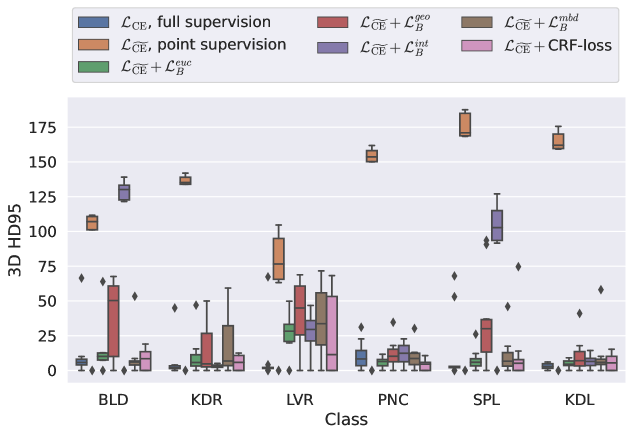

5.1 Segmentation of cardiac structures

The average 3D Dice scores and HD95 values on the ACDC test set are given in Table 2, and boxplots in figures 4 and 5 show the distributions. We see that, in terms of DSC, the proposed strategy of using intensity-aware distances withing boundary loss performs better than simply using the Euclidean distance, with the best results achieved by using the strictly intensity based MBD. The HD95 however favors the original version of , which may be do to its smoother predictions and less fragmentation and oversegmentation. The CRF-loss results are significantly worse in both metrics.

5.2 Abdominal organ segmentation

In Table 3, the average DSC and HD95 results are shown (both using 2D and 3D distance maps) for the task of abdominal organ segmentation in POEM data (for boxplots see figures 8 and 9). We see that training with and (with distances calculated on 2D slices) performs comparably, while using and produces lower scores in both DSC and HD95 metric. On this dataset, the CRF-loss is able to compete with the boundary loss-based training strategies, even outperforming them on most classes. Most notably, all models trained with boundary loss appear to have a hard time segmenting the liver. We hypothesize this may be due to extremely severe class imbalance, as the liver covers a very large area compared to the rest of the classes. It is thus also more strongly affected by undersegmentations.

Inspecting the values of training with on distance maps computed in 3D from Table 3, we notice that the results generally improve over values achieved by using 2D distance maps. Most notable decreases are visible in HD95 values, as using volume-calculated distance maps provides more global information and additionally penalizes spatially unreasonable segmentations. The methods based on are now able to compete with the CRF-loss, in particular the one.

While CRF-loss appears to perform very well on POEM data, it is also very slow to learn according to the validation curves in Figure 7. In Table 4 a quantitative comparison of the times per training iteration is given. We see that training by means of boundary loss with different distances incurs a small increase in iteration time, compared to training with only CE. However, the increase in time for the CRF-loss is much larger.